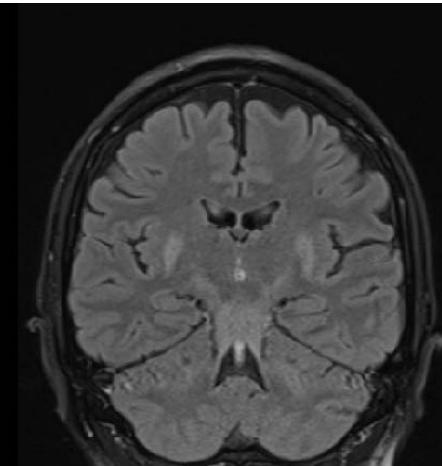

We report a rare case of Wilson’s Disease with neurologic features in a 31-year-old man. This disease consists of a disturbance of copper metabolism secondary to a mutation in the gene responsible for encoding the tissue transporter and the enzyme that incorporates the excess element into bile, generating toxic accumulation in the liver, cornea, and central nervous system. According to his wife, the patient had been treated for an unspecified mood disorder. The clinical picture was characterized by depressive mood, anhedonia, and anxiety. He had his first seizure episode on December 3rd, 2021. He progressed with dysarthria, ataxic gait, dystonia of the right-hand flexor muscles, and intermittent urinary incontinence. Marked worsening was observed after the diagnosis of COVID-19 in February 2022. At the clinical evaluation on March 24th, risorius muscle dystonia (risus sardonicus), resting tremor, and Kayser Fleischer rings at slit-lamp examination was also noted.